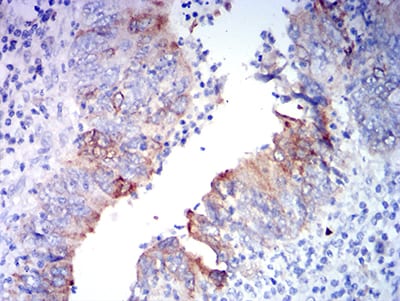

![GRIA2 Mouse mAb[63689]](https://img1.dxycdn.com/p/s14/2025/0922/579/6100930316915699691.jpg)

Immunohistochemical analysis of paraffin-embedded human rectum cancer tissues using GRIA2 mouse mAb with DAB staining.